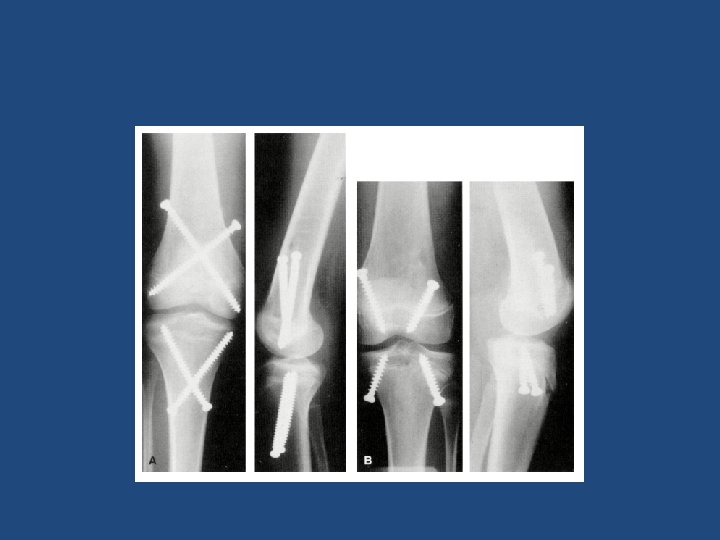

HISTORY In 1949, Blount set standard with epiphyseal stapling – Direct mechanical compression – Widely utilized and clinically proven Control of bone growth by epiphyseal stappling Blounts JBJS 1949

COMPLICATIONS • • • Breakage Migration Physeal closure Difficult removal Poor correction